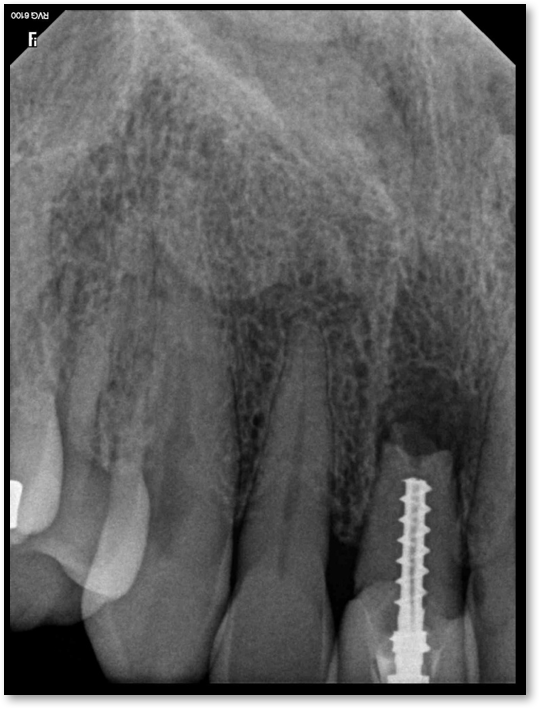

Adjacent Structures

If a tooth stands alone, greater forces will be placed on it because it has no adjacent teeth to provide support. This situation will affect the decision-making process for placing a post. Figure 3 shows a tooth that was on an island and would be having three implants placed in front of it. The tooth would take a much greater beating than another tooth that had support proximally. Even though it had a good root canal, the clinician would need to account for whether the tooth would last until the implants integrated. Figure 4 shows a case that would quickly proceed to implants. The patient had a less-than-ideal bridge for over a decade, with decent endodontics and functionality. There was also an overhang on the premolar. The post was not ideal in this case because there was one distal canal and not all the gutta-percha was removed from it. An intimate fit should be the goal with the post and the walls. Whether using a threaded or non-threaded post, there should not be excess gutta-percha because it is not as solid as the tooth and will lead to greater movement. That movement on the tooth and bridge will create too much force and result in demise.

Fig 3. Tooth on an island.

Figure 3